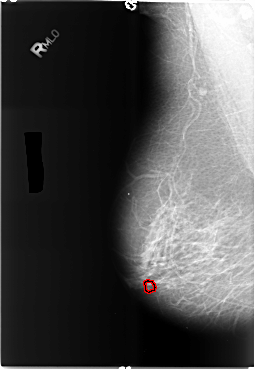

B_3489_1.RIGHT_MLO

FILE: B_3489_1.RIGHT_MLO.OVERLAY

TOTAL_ABNORMALITIES 1

ABNORMALITY 1

LESION_TYPE CALCIFICATION TYPE ROUND_AND_REGULAR-PLEOMORPHIC DISTRIBUTION CLUSTERED

ASSESSMENT 4

SUBTLETY 3

PATHOLOGY BENIGN

TOTAL_OUTLINES 1

BOUNDARY